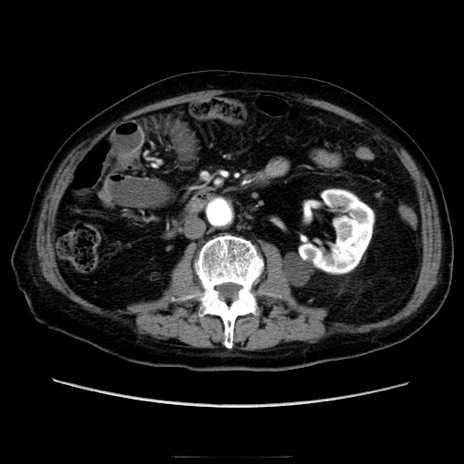

症例21(横断像)

【症例】70歳代男性

【主訴】腹痛

【現病歴】肝硬変・肝細胞癌にてかかりつけの方。約9時間前に食後より腹痛出現。症状が徐々に増悪し、嘔吐出現したため来院。

【既往歴】肝硬変、肝細胞癌(RFA、TACE後)

【身体所見】意識清明、表情苦悶様、BT 36℃、BP 129/78mmHg、P 88bpm、SpO2 97%(RA)、右上腹部から心窩部にかけて圧痛あり、反跳痛なし、筋性防御あり。

【データ】WBC 5800、CRP 0.16